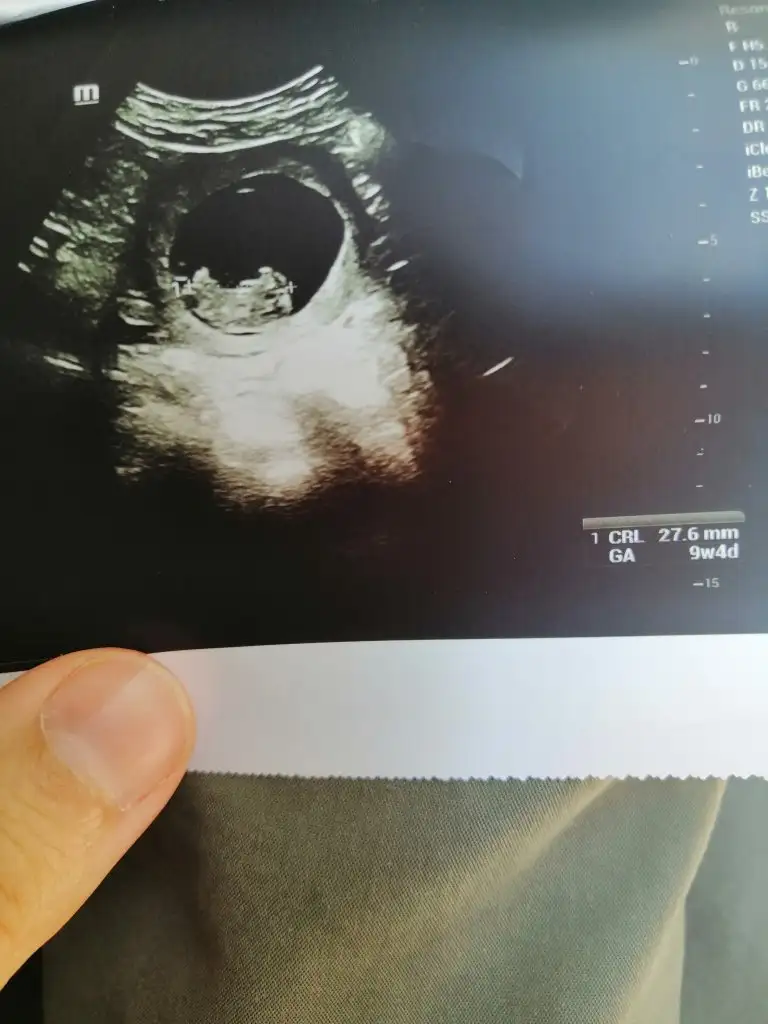

maşallahKızlar buda benim bebişim bugün gittim yorumlayın bakalim kiz mi erkek mi

Amin canım hepimizinki insallah Allah'ım sağlıkla kucağımıza almayı nasip etsinmaşallahben kıza benzettim canım. hayırlı evlat olur inşallah

Kız gibi yuvarlak keseden dolayıBenim tırtıklı cipsime bakın bir de

Kız büyük ihtimalle:)Kızlar buda benim bebişim bugün gittim yorumlayın bakalim kiz mi erkek mi